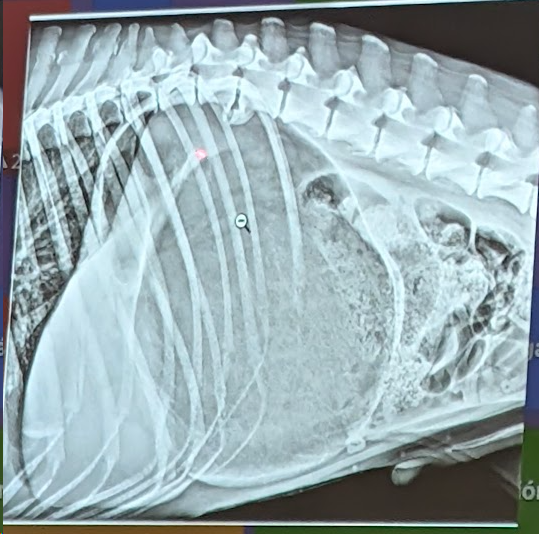

Preguna 6 - Multiple respuesta

- Hay un desplazamiento dorsal del piloro (por torsion estomacal)

- Signo de doble burbuja ( presencia de dos compartimentos llenos de gas en el estómago por el giro, el cual aparece distendido y rotado.)

- Torsión Gastrica

- Hay una dilatación gastrica (por torsión)